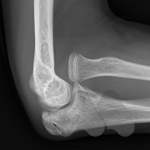

Dislocations are commonly a result of trauma causing the joint to move out of its normal position and relationship with other bones. Dislocations can be accompanied by fractures. Sometimes the dislocation causes an obvious deformity and can be pulled or pops back into position on it’s own. In some situations, the joint cannot be pulled back into position or keeps falling out of position due to tissues such as bone fragments blocking the reduction or due to torn ligaments or fracture through supporting bones. In this situation, you may need to have some form of anaesthetic to realign the bones in the Emergency department or operating theatre or in some cases, the joint being opened and surgically stabilised.